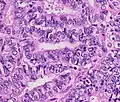

Endometrioid adenocarcinoma

In endometrioid adenocarcinoma, the cancer cells grow in patterns reminiscent of normal endometrium, with many new glands formed from columnar epithelium with some abnormal nuclei. Low-grade endometrioid adenocarcinomas have well differentiated cells, have not invaded the myometrium, and are seen alongside endometrial hyperplasia. The tumor's glands form very close together, without the stromal tissue that normally separates them. Higher-grade endometrioid adenocarcinomas have less well-differentiated cells, have more solid sheets of tumor cells no longer organized into glands, and are associated with an atrophied endometrium. There are several subtypes of endometrioid adenocarcinoma with similar prognoses, including villoglandular, secretory, and ciliated cell variants. There is also a subtype characterized by squamous differentiation. Some endometrioid adenocarcinomas have foci of mucinous carcinoma.[47]

The genetic mutations most commonly associated with endometrioid adenocarcinoma are in the genes PTEN, a tumor suppressor; PIK3CA, a kinase; KRAS, a GTPase that functions in signal transduction; and CTNNB1, involved in adhesion and cell signaling. The CTNNB1 (beta-catenin) gene is most commonly mutated in the squamous subtype of endometrioid adenocarcinoma.[48]

The histopathology of endometrial cancers is highly diverse. The most common finding is a well-differentiated endometrioid adenocarcinoma,[49] which is composed of numerous, small, crowded glands with varying degrees of nuclear atypia, mitotic activity, and stratification. This often appears on a background of endometrial hyperplasia. Frank adenocarcinoma may be distinguished from atypical hyperplasia by the finding of clear stromal invasion, or "back-to-back" glands which represent nondestructive replacement of the endometrial stroma by the cancer. With progression of the disease, the myometrium is infiltrated.[60]

Metastatic endometrial cancer seen in a removed lung_grade_1_endometrial_adenocarcinoma.png.webp) Grade 1: ≤5% solid non-glandular, non-squamous growth.[61]

Grade 1: ≤5% solid non-glandular, non-squamous growth.[61] Grade 2: >5% and ≤50% solid non-glandular, non-squamous growth.[61]